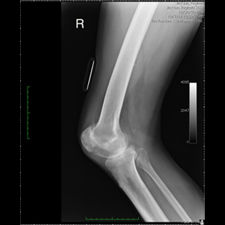

Bilateral Total Knee Replacement was recommended, and performed on July 27th 2011. Since surgery, the patient has made good progress and can now mobilize with the aid of a walker.

His x-rays and clinical examination suggest good early outcome with a fully mobilized patient with pain free knees and the ability to walk independently.

At the present time, he remains under our care and with physiotherapy and self-exercise, he will continue to improve.